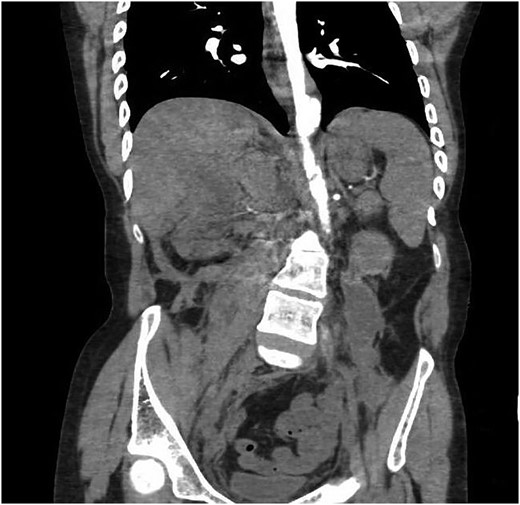

Our patient is a 24-year-old male with the EDS type VI who had undergone rod fixation of his spine for scoliosis, ocular surgery for a ruptured globe and ligation of his popliteal artery after an attempt was made to repair his aneurysm. The patient was being followed at Duke EDS Clinic where he underwent an extensive workup, and a definitive diagnosis was established. He presented to the emergency room (ER) after being kicked in the abdomen during a martial arts class. The patient felt an instant abdominal pain which resolved quickly. The patient went home after the incident and then developed nausea, vomiting and diaphoresis. He was hemodynamically normal in the ER. His groin pulses were slightly diminished compared with his radial pulses. The patient underwent a computed tomography (CT) scan of the chest, abdomen and pelvis with intravenous contrast. The patient was found to have traumatic aortic injury (Fig. 1). Cardiovascular surgery was consulted. The patient was admitted to the ICU for nonoperative therapy. He was started on Esmolol intravenously, and Diltiazem was added in order to keep his mean arterial pressure around 60. After 2 days in the ICU, the patient was transitioned to medications by mouth. He was allowed to ambulate on the fourth day and discharged on the eighth day after a long discussion with him and his family.